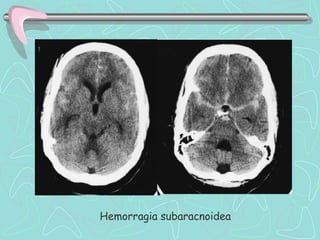

02.    HEMORRAGIA SUBARACNOIDEA . HSA

 Extravasación de sangre al espacio subaracnoideo

encefálico.

 Primaria. Sangrado directo al espacio subaracnoideo

 Secundaria. Sangrado inicialmente en el parénquima

cerebral.

 Principalmente debida a la rotura de aneurismas

arteriales,

DIAGNÓSTICO

•TC ENCÉFALO :

Hemorragia en Espacio Subaracnoideo.

Sensibilidad    95% 1ºdía;

50% 7ºdía

•Si TC Encéfalo es negativo: Punción Lumbar

•LCR CENTRIFUGADO :

Xantocromía de sobrenadante,

Crenocitos,

Prueba de tres vasos positivo.

Hemorragia subaracnoidea